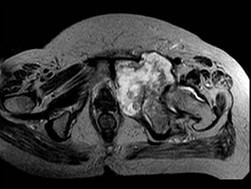

问题 患者 男,38岁,感觉左髋部疼痛,并逐渐加重,体检:左髋部明显肿胀压痛,无明显发热,请选择最佳诊断 ( )

选项 A、软骨肉瘤 B、软骨黏液纤维瘤 C、纤维肉瘤 D、骨肉瘤 E、骨巨细胞瘤

答案 A